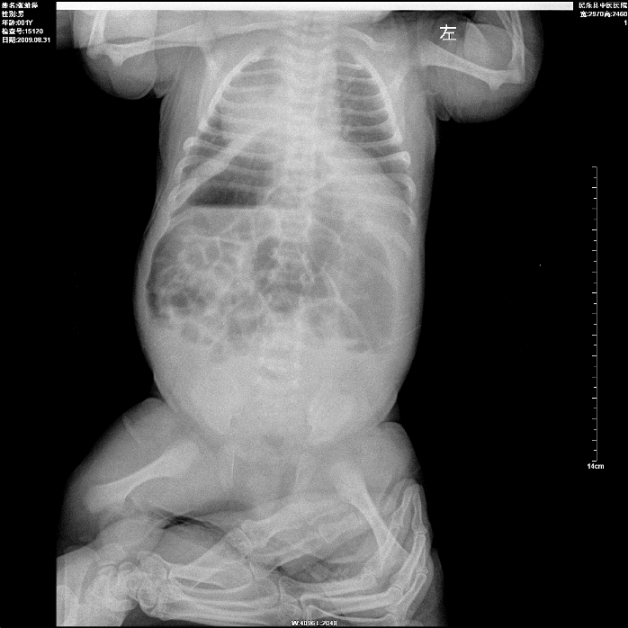

标题: PED2878:男性,1月.腹部胀满,哭闹烦躁不安2天.请大家看看是否 [打印本页]

空腔脏器穿孔并气腹?膈疝?建议ct进一步检查。

内脏反位?坏死性肠炎?

内脏反位,小儿胃肠胀气非常常见,有否气腹要立位观察。

胃泡充气肠气郁,不知大便如何,膈疝与肠套叠均不能排除,建议作进一步检查或复查为妙。

另婴幼儿拍片一般是前后位,如果技师没标错左右的话,就是还有全内脏反位,

内脏反位可能,膈膨升?肠道动力性改变。1岁以下小儿小肠、结肠都充气,是正常的,2岁以后就和成人一样了,只有结肠充气,小肠不充气,反之就考虑梗阻的可能。胸部阴影,除了有心脏还有胸腺的影子。